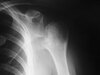

Baseball player, adolescent with this xray? What is it and next steps?

**Little Leaguer’s shoulder**, physeal widening. This condition is secondary to overuse (typically throwing) and responds well to rest from the inciting activity. The changes in the proximal humerus are classic for this condition and are not suggestive of a neoplastic process requiring biopsy for definitive diagnosis. **tx: rest from throwing activities.** cessation of throwing, then PT and progressive throwing program after sufficient rest. OB: repetitive torsional & distractive stresses at physis SHI. Hypertrophic zone (weakest portion of physis) Late cocking: 400% greater external rotatory force than physis can tolerate. Deacceleration: excessive eccentric stress Breaking pitches implicated # of pitches most important factor Complication: Premature growth arrest of proximal humeral epiphysis ## Footnote prevention: proper pitching mechanics, discourage breaking ball pitches, enforcement of pitch counts, avoid year round pitching.